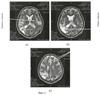

Визуально при магнитно-резонансной томографии выявили в медиобазальных отделах правой теменной доли постишемический очаг с нечеткими неровными контурами (фиг.3а) острого нарушения мозгового кровообращения по ишемическому типу размером 2,9×3,2×2,6 см; в медиальных отделах левой височной доли округлый постишемический очаг с четкими неровными контурами размером 3,5×2,1 см (фиг.3б); в белом веществе субкортикальных отделов лобных и теменных долей множественные мелкие постишемические очаги размерами до 0,4 см (фиг.3в). Определили наличие смешанной заместительной гидроцефалии. Отметили многоочаговость и асимметричность поражения церебральных структур с локализацией очагов как в базальных отделах, так и субкортикальных зонах обоих полушарий мозга.

С экрана дисплея вычислили реальные величины линейных параметров на трех последовательных срезах, начиная с уровня базальных ганглиев, таламуса и выше. На уровне базальных ядер таламуса определили максимальную ширину сильвиевых борозд справа (11 мм) на фиг.4а и слева (5 мм) на фиг.4а; на уровне визуализации сосудистых сплетений желудочков головного мозга – ширину задних рогов боковых желудочков справа (12 мм) на фиг.4б и слева (13 мм) на рис 4б и максимальное расстояние между внутренними пластинками костей черепа (139 мм) на фиг.4б; на уровне центральных частей боковых желудочков – минимальную ширину правого (8 мм) на фиг.4в и левого (11 мм) на фиг.4в тел боковых желудочков. Дополнительно рассчитали суммарный когнитивный индекс по предложенной формуле: СКИ=(11+5+12+13+8+11)/139=0,43. Сопоставили вычисленный индекс, равный 0,43, с его критическим значением 0,44. Вычисленный индекс выше значения 0,44, значит прогнозировать развитие постинсультной деменции мы не можем. На 19-е сутки болезни осмотрен психиатром в связи с наличием анозогнозии. Заключение психиатра: психические нарушения на момент осмотра не выявлены.